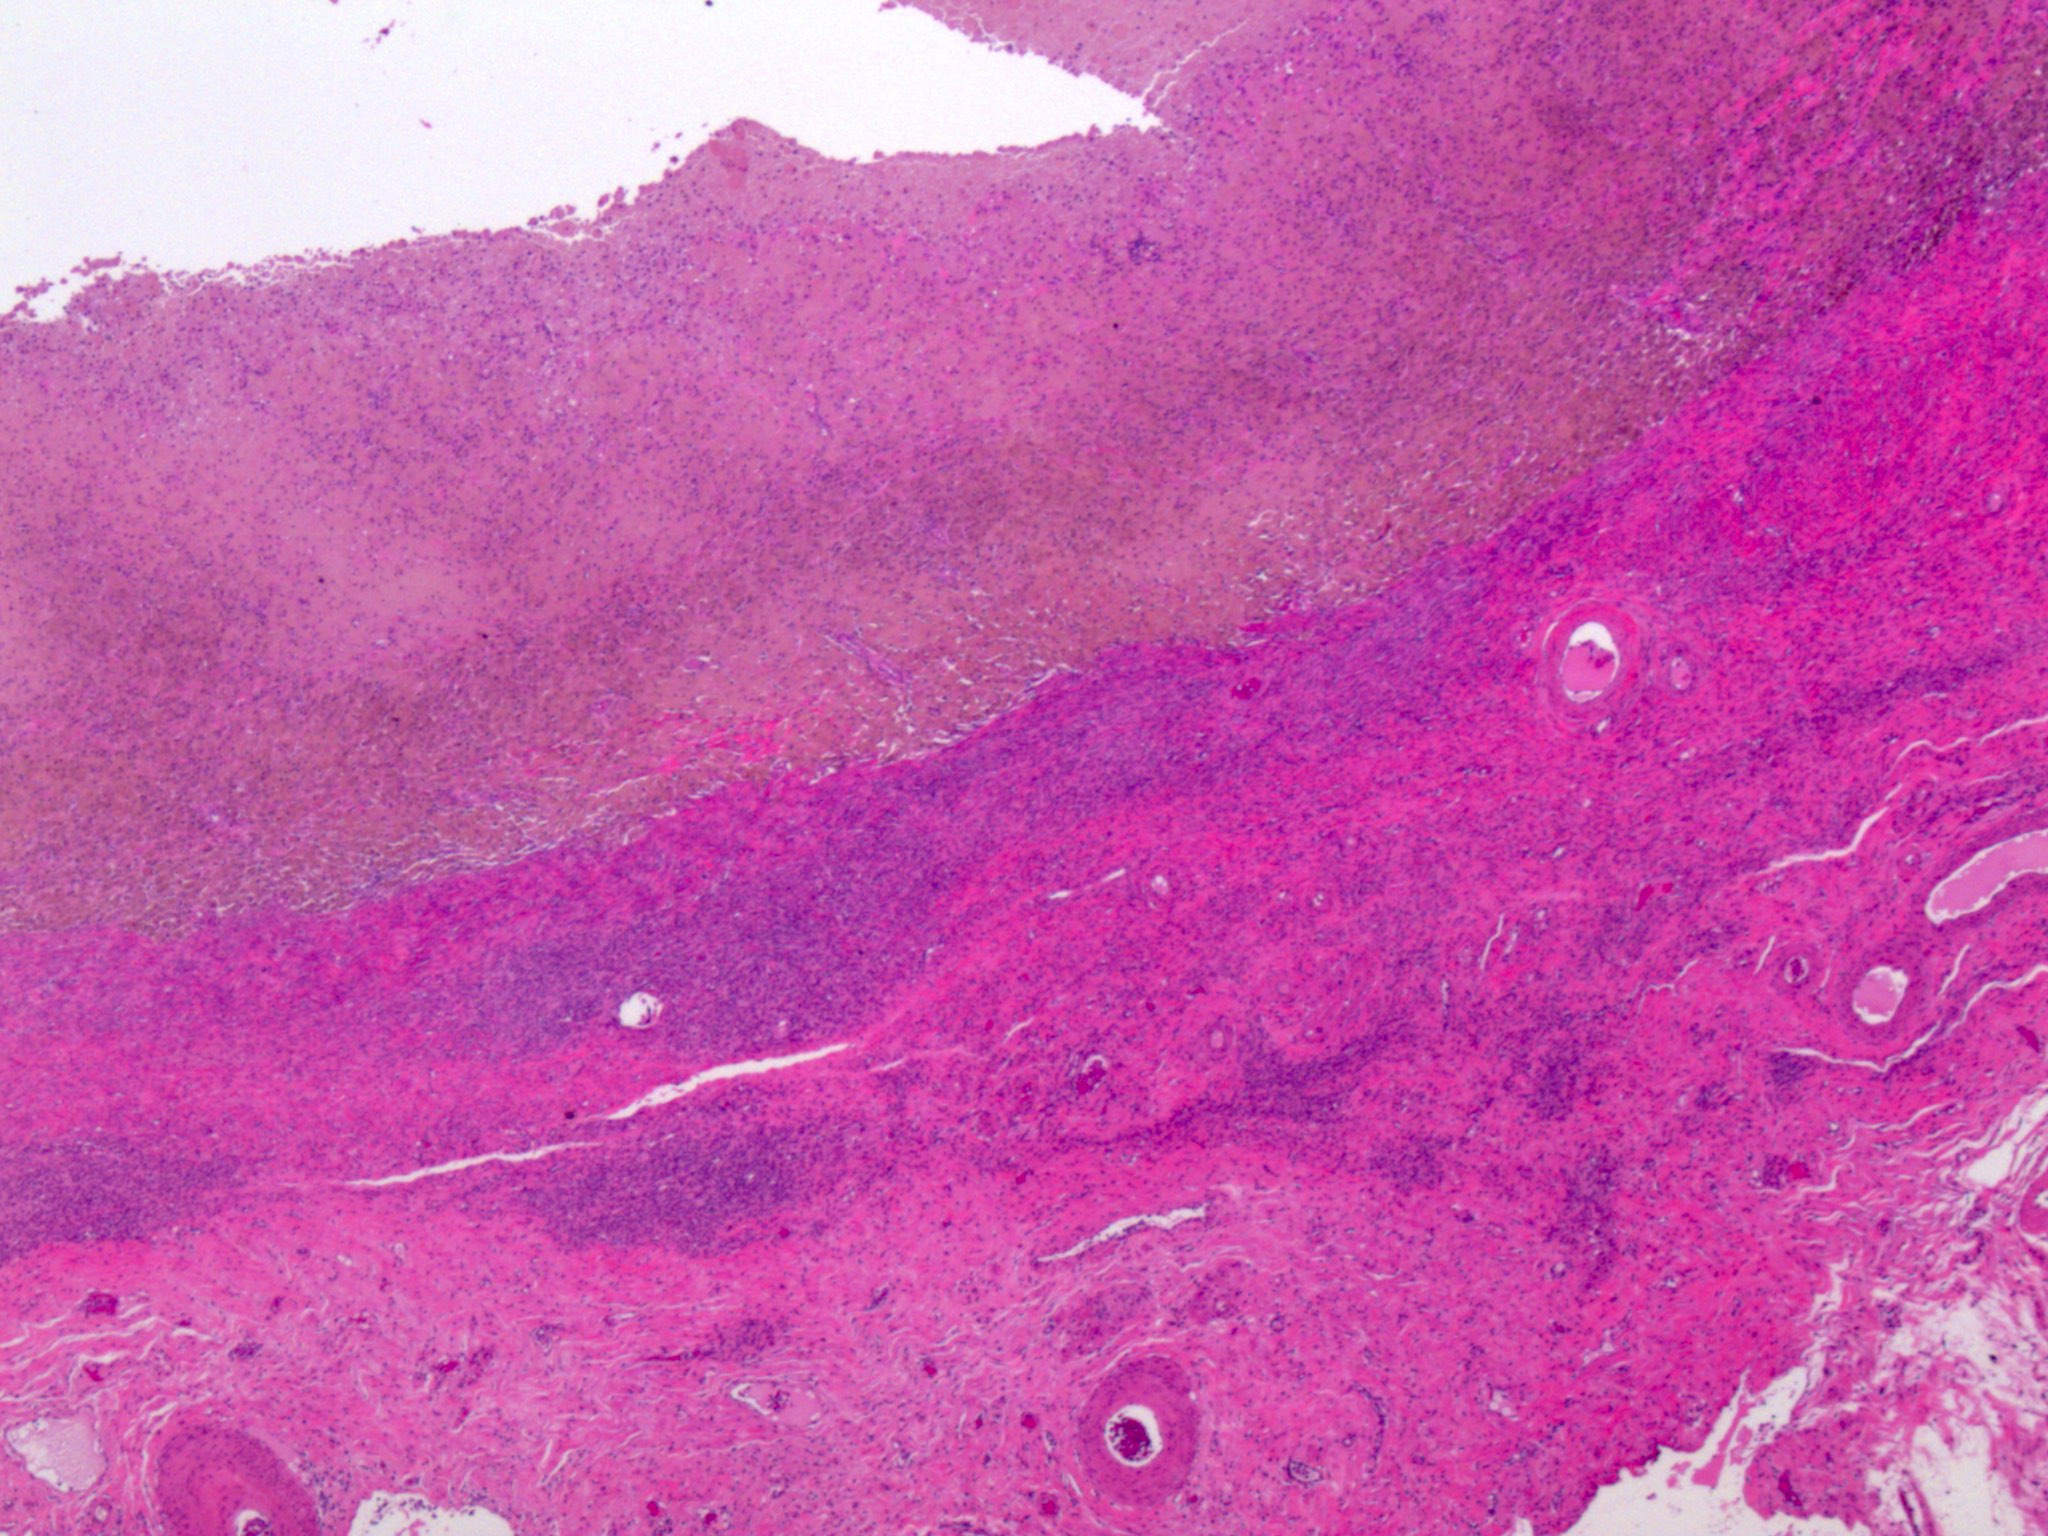

Microscopic (histologic) images

Microscopic (histologic) description

- At least 2 of the following 3 features

- Evidence of chronic hemorrhage (hemosiderin laden or foamy macrophages)

- Necrotic pseudoxanthomatous nodules: central necrosis surrounded by histiocytes and outer fibrous zone

- Liesegang rings: eosinophilic acellular rings within necrotic tissue (Histopathology 2020;76:76)

- Burnt out endometriosis: this term has been proposed for changes suggestive of endometriosis, such as central necrosis with surrounding fibrosis and pseudoxanthoma cells but lacking confirmatory features as listed above